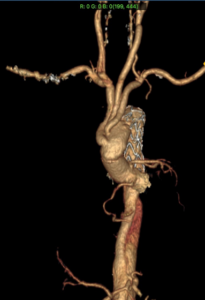

Hình ảnh sau mổ: Gốc động mạch chủ, động mạch chủ ngực nhân tạo có hình thái bình thường, các động mạch nuôi não được phục hồi, stent graft động mạch chủ xuống thông tốt làm tăng kích thước lòng thật động mạch chủ ngực bụng.

Quá trình thực hiện phẫu thuật bắt đầu bằng tái thông động mạch cảnh trái để đảm bảo nuôi não tối ưu. Sau đó là thực hiện đặt stent graft trong quá trình hạ thân nhiệt sâu, ngừng tuần hoàn nửa dưới cơ thể và tưới máu não chọn lọc. Vùng gốc động mạch chủ phồng lớn đòi hỏi phải tạo hình lại với sửa chữa hoặc thay thế van tim, bên cạnh phục hồi lại lưu thông các động mạch vành. Các bác sĩ đã quyết định sửa chữa gốc động mạch chủ với phương pháp bảo tồn van để tránh cho bệnh nhân phải sử dụng thuốc chống đông liều cao cả đời nếu phải thay van nhân tạo. Công đoạn quan trọng cuối cùng là phục hồi các động mạch nuôi não, trong đó có vị trí phục hồi động mạch cảnh trái ở sát vùng góc hàm, ngay tại ngã ba các động mạch cảnh. Sau quãng thời gian dài xuyên đêm, đến thời điểm bắt đầu ngày làm việc mới, trái tim của người bệnh đã hồi phục với sức co bóp tốt, cấu trúc và chức năng van tim tương đối bình thường khi siêu âm tim thực quản ngay trong mổ.

Với sự phối hợp nhịp nhàng giữa các bác sĩ Trung tâm Tim mạch và Gây mê hồi sức, ca phẫu thuật đã diễn thành công. Chỉ sau 3 ngày phẫu thuật, người bệnh đã được rút nội khí quản, hoàn toàn tỉnh táo, chức năng các tạng được duy trì ổn định. Các kết quả chẩn đoán hình ảnh của người bệnh trước khi ra viện cũng cho thấy khối phồng động mạch chủ được xử lý triệt để, động mạch vành bị tắc được tái tạo, van hai lá sau tạo hình và kích thước buồng tim trở lại giống như ở người bình thường.